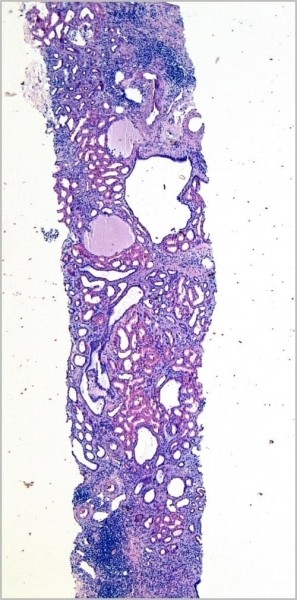

Фото 1.Приведу пример — заболевание у брата (13 лет) и сестры (9 лет) с неотягощенной наследственностью, у которых с раннего возраста отмечался упорный энурез. На фоне переносимой инфекции практически одновременно у детей ухудшилось самочувствие, и они были госпитализированы. На УЗИ были выявлены выраженные диффузные изменения в паренхиме обеих почек без значимого изменения их размеров.

Была выполнена нефробиопсия, которая показала у обоих детей схожие изменения в ткани почек, связанные с образованием множества канальцевых кист (см. фото 1) с выраженной круглоклеточной инфильтрацией и фиброзом стромы, атрофией канальцевого эпителия, утолщением и удвоением базальных мембран (в том числе неатрофичных канальцев) (см. фото 2).

Фото 2.

На основании клинических и морфологических изменений детям был выставлен диагноз достаточно редкого наследственного заболевания — комплекс «нефронофтиз — медуллярная кистозная болезнь». наследуется аутосомно-рецессивно, но так совпало, что оба ребенка в семье получили именно тот ген, который привел к развитию болезни. На данный момент пациенты вышли на ХПН и перенесли пересадку почек.